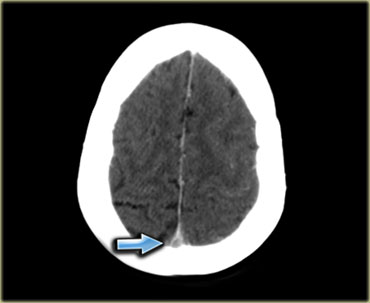

Nhồi máu tĩnh mạch (2) – Huyết khối xoang tĩnh mạch dọc trên

Cấu trúc tĩnh mạch bị huyết khối thường gặp nhất là xoang tĩnh mạch dọc trên.

Nhồi máu gặp trong 75% các trường hợp.

Các bất thường có vị trí cạnh đường giữa và thường có tính chất hai bên.

Xuất huyết gặp trong 60% các trường hợp.

Hình ảnh bên trái cho thấy phù nề cạnh đường giữa hai bên và xuất huyết nhỏ ở bệnh nhân huyết khối xoang tĩnh mạch dọc trên.

Hình ảnh bên trái là tái tạo CT mặt phẳng đứng dọc của một bệnh nhân có xuất huyết cạnh đường giữa hai bên do huyết khối xoang tĩnh mạch dọc trên.

Mũi tên đỏ trên hình CT có tiêm thuốc cản quang chỉ khuyết thuốc do huyết khối gây ra.